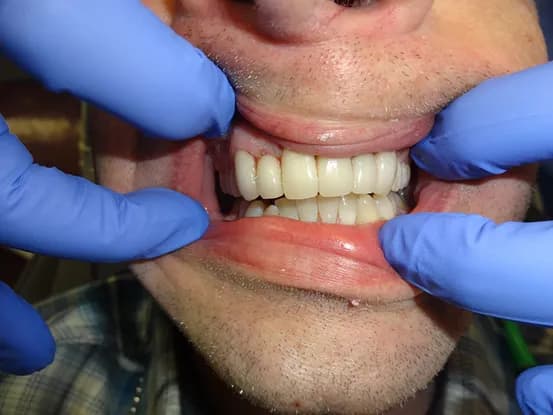

Case 2

64 year old male with severe grinding TMJ issues resulting in a 6 mm bite collapse. Root canals done on exposed teeth and full mouth rehabilitation with porcelain fused to metal crowns performed to restore proper form and function of dentition.